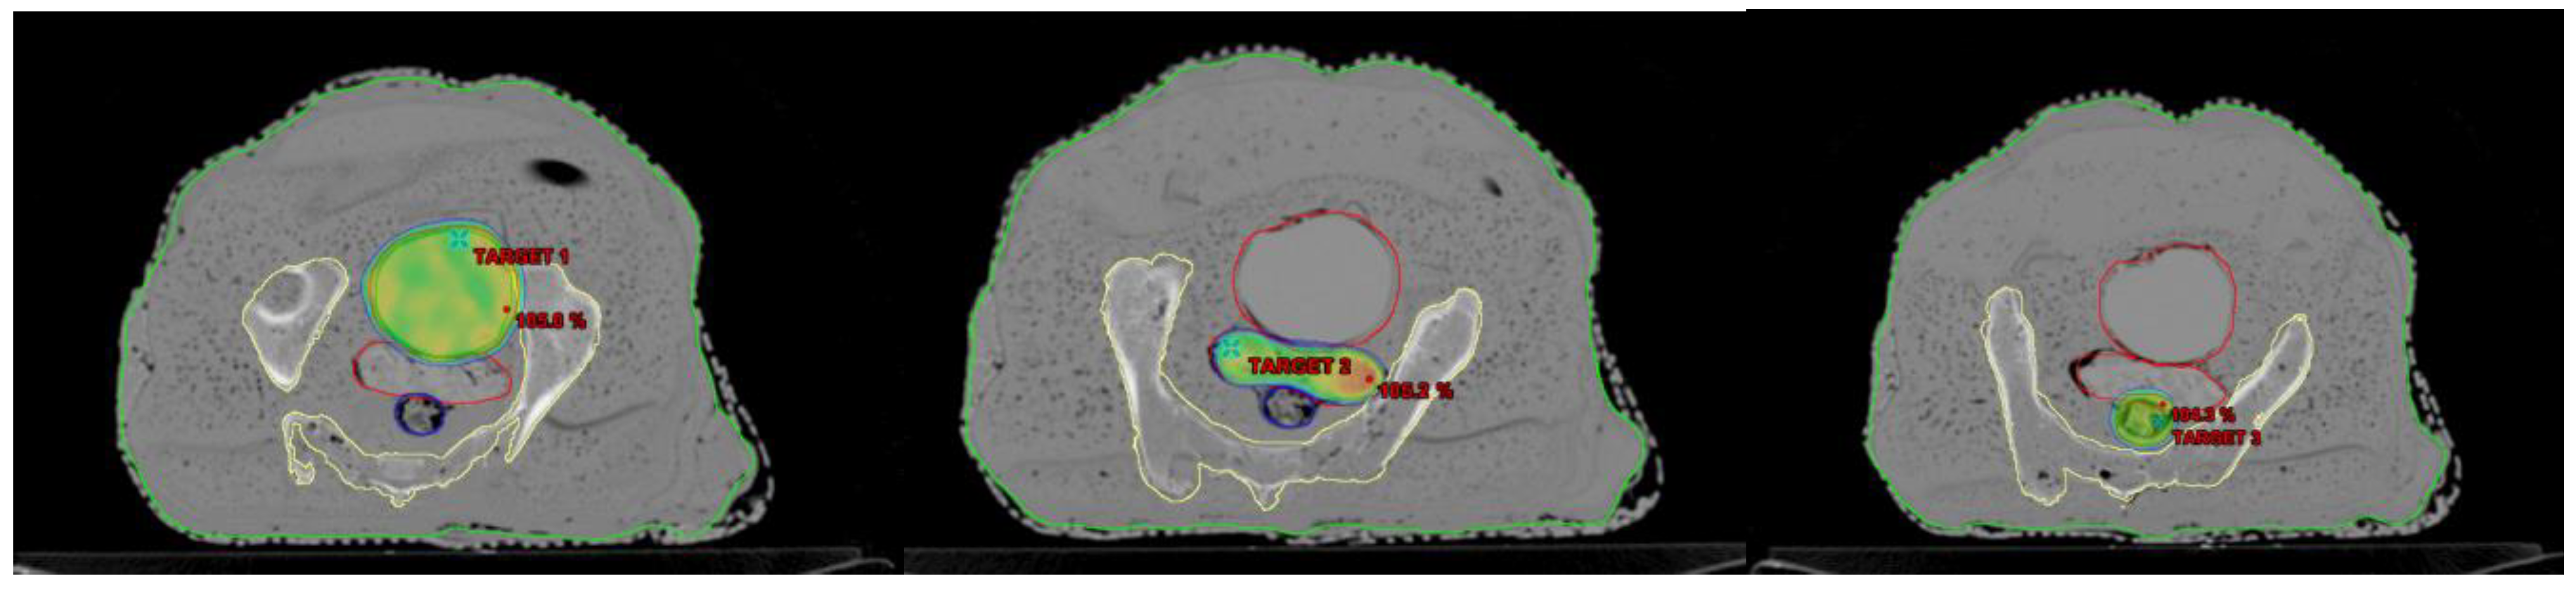

2.5.2. Relative Dosimetry

To evaluate the effectiveness of the AHFP phantom as a quality assurance (QA) tool, planning target volumes (PTVs) were generated for the phantom. To assess the dose received by healthy organs during radiation therapy, organs at risk (OARs), like the bladder and rectum, were also considered. Both RapidArc and intensity-modulated radiation therapy (IMRT) plans were created on a treatment planning system (TPS), and the anisotropic analytical algorithm (AAA) (version 11.0.31) was used to calculate the dose. The 2D fluence generated by the TPS on the electronic portal imaging device (EPID) was sent to the linear accelerator (linac) for further analysis, which is represented in Figure 4. Most modern linacs are equipped with flat-panel detectors based on amorphous silicon (aS1000 model) for megavoltage imaging. Various methods have been developed to utilize EPIDs in IMRT/RapidArc patient-specific quality assurance (PSQA). All measurements were carried out using an EPID detector calibrated for a 100 cm source-to-imager distance (SID). Data collection was performed with the same gantry and collimator positions specified in the treatment plan.

Figure 4.

Displaying three different targets on the AHFP Phantom for dose verification.

The imaging system software was employed to compare and analyze the 2D fluence imaging obtained from the treatment planning system (TPS). For plan evaluation, pixel-based passing criteria were utilized. A pass condition was set at an average gamma value (g) of ≤1, indicating successful plan agreement, while a failure condition was defined as g > 1, indicating discrepancies. In our assessment, we used specific tolerance levels as acceptance standards. These included a distance-to-agreement (DTA) of 3 mm, representing the maximum allowed spatial difference between the measured and expected dose distributions. Additionally, a dose difference (DD) of 3% was considered, signifying the permissible variation between the measured and expected doses.

The results obtained from relative dosimetry are tabulated in Table 5. The average gamma values of the RapidArc plans are 0.29, 0.32, and 0.35 (g ≤ 1), and these values for the IMRT plans are 0.45, 0.44, and 0.42 (g ≤ 1) for targets 1, 2, and 3, respectively.

In Table 5, we present a comprehensive assessment of all planned target locations on the AHFP phantom, utilizing both RapidArc and IMRT treatment techniques. The table provides essential parameters, including area gamma, maximum dose difference, and average dose difference, for each target location. The results highlight the remarkable agreement between the measured and expected dose distributions, as indicated by the area gamma values ranging from 97.9% to 99.8% across all target locations. This excellent level of concurrence underscores the AHFP phantom’s ability to faithfully replicate radiation interactions and accurately deliver doses to the intended target volumes. Examining the maximum dose difference, we observe variations ranging from 18.7% to 39.4% for the different target locations. Additionally, the average dose difference ranges from 1.1% to 2.5%. These values, although demonstrating some variability, remain well within acceptable tolerance limits for relative dosimetric purposes. Our research findings are in line with the study conducted by Smith et al. [38]. By utilizing the gamma index approach, both studies assessed the agreement between calculated and measured dose distributions, which provided crucial insights into the accuracy of treatment planning. The study by Smith et al. reinforces the significance of gamma index analysis as a valuable and comprehensive tool for dosimetric evaluation, further validating its importance in radiation therapy quality assurance and treatment optimization.